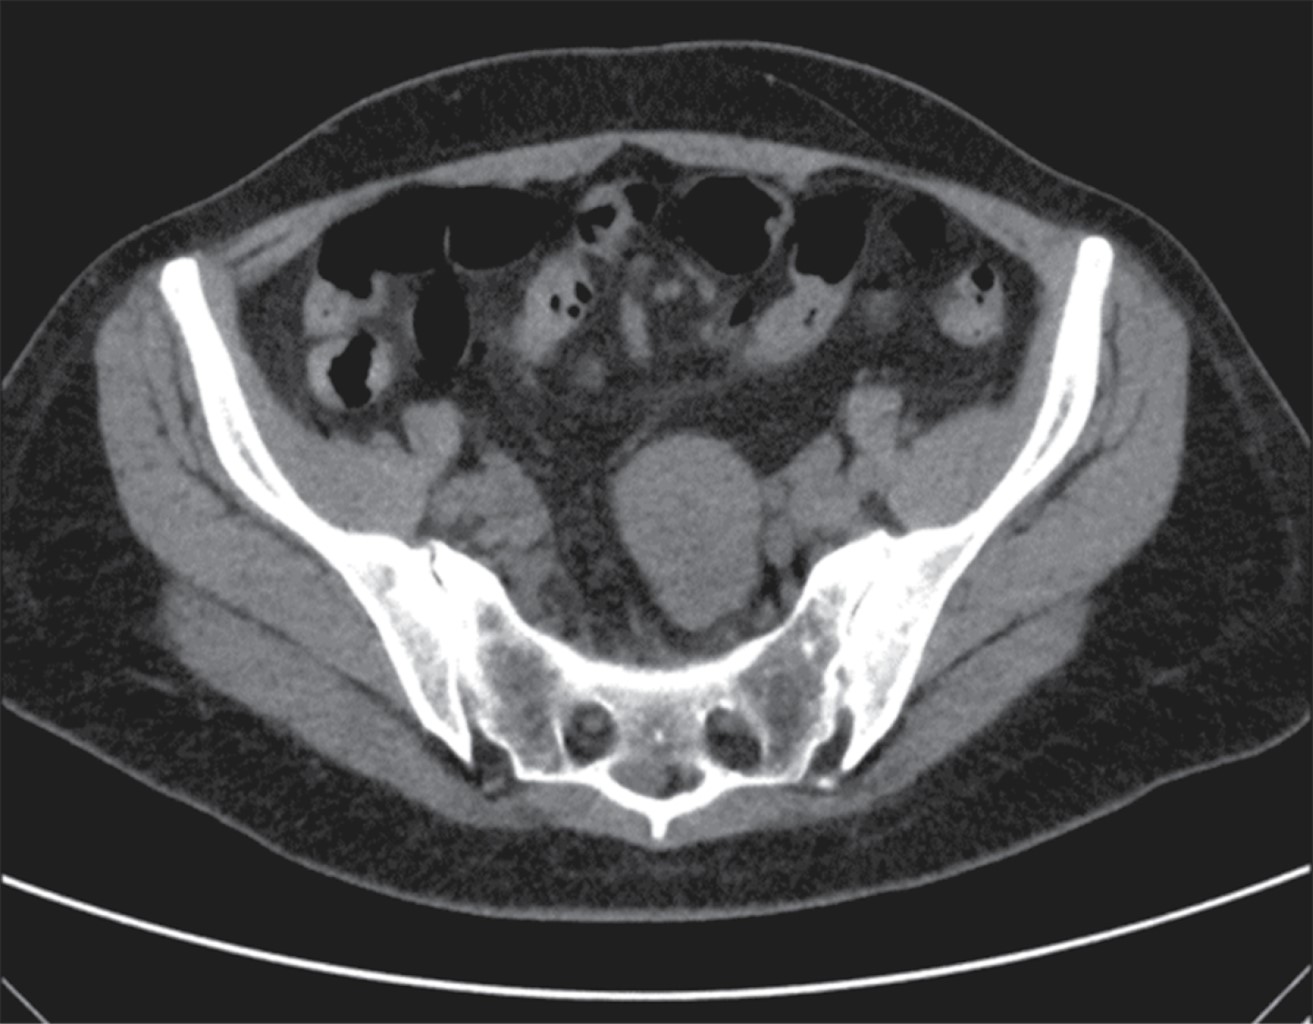

An abdominal ultrasonography (USG) scan was performed, reporting an image of a tumor in the right iliac fossa measuring 10.5 × 5.5 × 9.9 cm. The colonoscopy study showed no evidence of tumor in the rectum and colon, and an apparent extrinsic compression at the ileocecal valve orifice (Figure 1).

A computed axial tomography (CT) scan showed a stenosing and infiltrative tumor of the ileum walls with a narrow lumen and distended bowel loops (Figures 2 and 3).

Figure 1

Figure 2